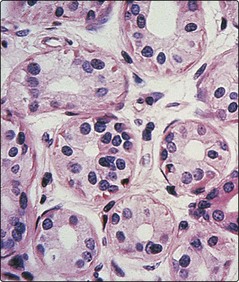

Sweat glands (Fig. 4) are tube-like and coiled glands, located within the dermis, which produce a watery secretion. There are two separate types: eccrine and apocrine.

image

Fig. 4 Sweat gland.

A cross-section through the coiled secretory portion of an eccrine sweat gland, situated deep in the dermis.

Eccrine sweat glands develop from downbudding of the epidermis. The secretory portion is a coiled structure in the deep reticular dermis; the excretory duct spirals upwards to open onto the skin surface. An estimated 2.5 million sweat ducts are present on the skin surface. They are universally distributed, but are most profuse on the palms, soles, axillae and forehead where the glands are under both psychological and thermal control (those elsewhere being under thermal control only). Eccrine sweat glands are innervated by sympathetic (cholinergic) nerve fibres.